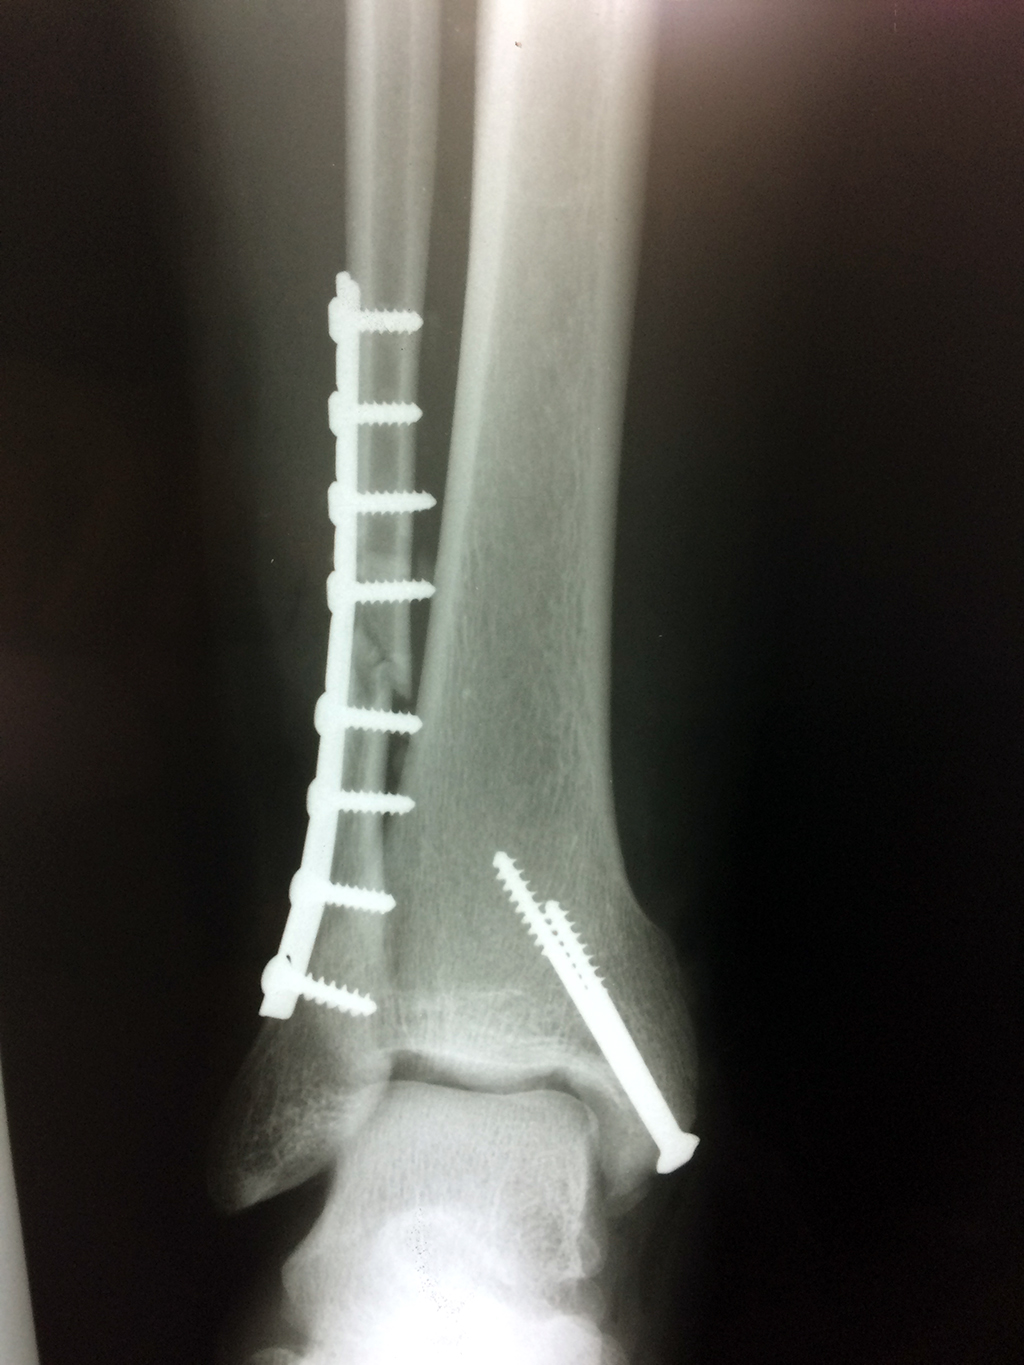

Cuando se necesita cirugía, es probable que esta implique el uso de clavijas de metal, tornillos o placas para sostener los huesos en su lugar mientras la fractura se consolida. Los elementos de soporte pueden ser temporales o permanentes.